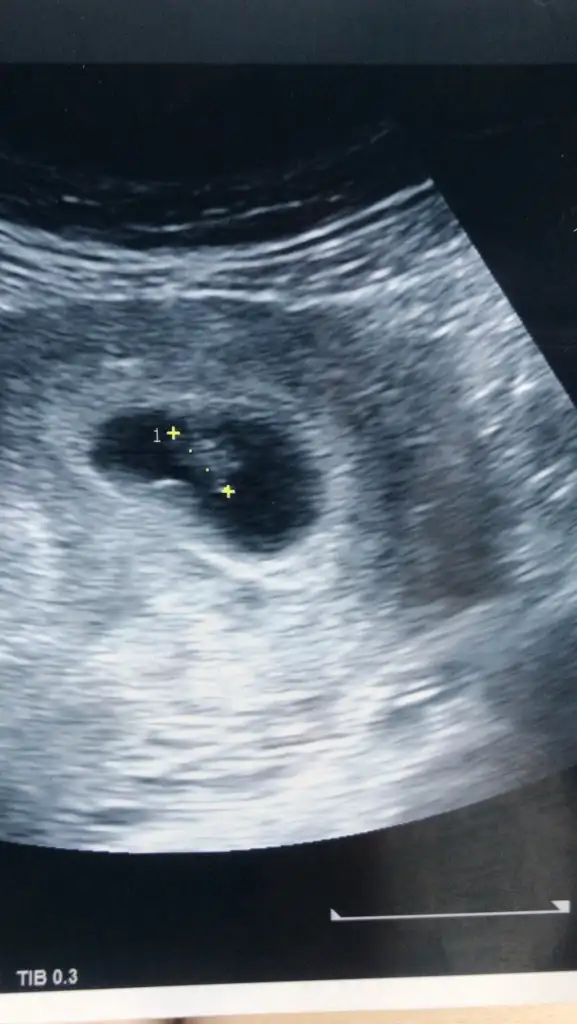

Cinsiyet tahmini alabilir miyim

• IMG_20240219_161530.webp

IMG_20240219_161530.webp

23,7 KB · Görüntüleme: 71